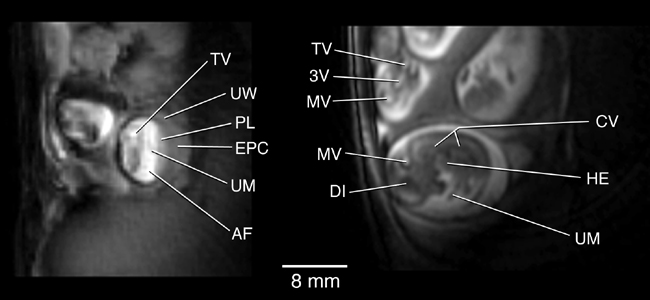

The first published images of time-course imaging of embryos in-utero using magnetic resonance imaging. The images show several rat embryos in coronal and sagittal views of the uterus.(Smith, Shattuck, Hedlund and Johnson. Magn Res Med, 39:673-677, 1998).